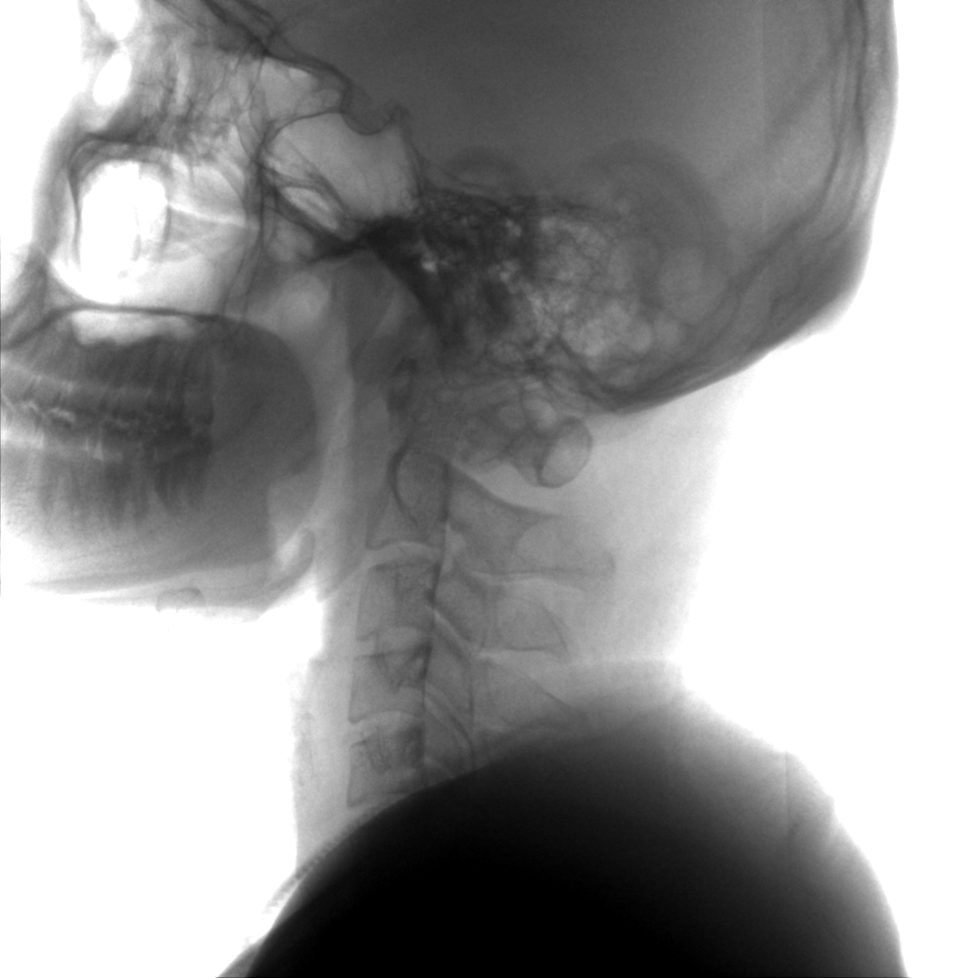

術(shù)中三維成像和橫斷面圖像提供多角度的手術(shù)診斷信息,輔助醫(yī)生進(jìn)行術(shù)中評(píng)估判斷,諸如骨折復(fù)位情況和內(nèi)植入螺釘?shù)某叽绾臀恢?,輔助手術(shù)更好地完成。

提供更大的術(shù)中三維成像視野,采集更多圖像信息,可一次拍全全段頸椎、全段腰椎、七節(jié)胸椎、雙側(cè)骶髂關(guān)節(jié)、股骨頭及單側(cè)盆骨。